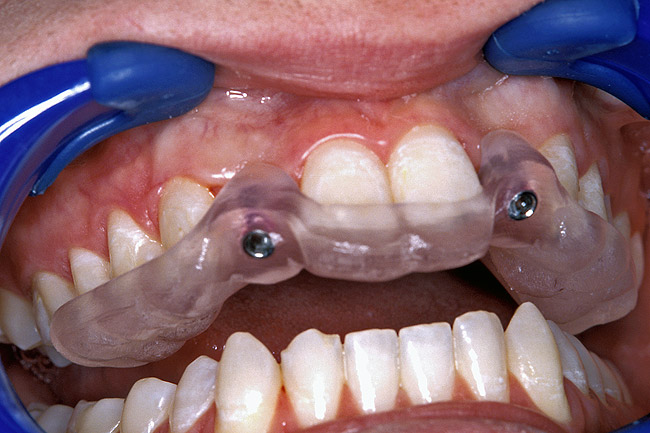

Before the day of surgery, the patient was seen by the orthodontist for the removal of the orthodontic brackets. The patient still was not pleased with the position of the two centrals, and it was determined that this would be addressed after implant placement (Figure 13A). The anatomical variations of the crestal tissue and lack of interdental papilla can be appreciated in the close-up views of the right and left sites (Figure 13B and 13C). There were no surprises on the day of surgery as all of the decisions were made during the planning phase, before the scalpel ever touched the patient. The occlusal view of the CT 3D model revealed the wider alveolar ridge on the right side and thinner crest on the left side (Figure 14A). This was confirmed when the full thickness mucoperiosteal flaps were elevated, and the underyling bone revealed (Figure 14B). The tooth-borne templates were designed to facilitate the drills and drilling sequence specific to the diameters of the predetermined implants (Figure 15A). Each template contained an embedded 5-mm long stainless steel tube, which was approximately 0.2-mm wider than each drill (just wide enough to allow for the drills to rotate freely). Once positioned over the natural teeth, the template was secure and offered precision accuracy in transferring the implant locations from the original software-designed plan, allowing the potential for internal and external irrigation (Figure 15B). The 3.7-mm diameter Tapered Screw-Vent implant drilling sequence requires three drills: pilot, intermediate, and final sizing. Thus, three separate templates were fabricated to a.commodate these sizes. The templates were removed easily and replaced with the next sequential size in less time than it takes to change the drill on the surgical handpiece. After the osteotomies had been.completed, the implants were delivered to the site (Figure 16A and Figure 16B). For this internal hex connection implant, the author r.commends that the flat of the antirotational hex be positioned to the facial for proper orientation of the restorative.components (Figure 17A). Preprepared margins were created from a milled titanium fixture mount transfer post, which was delivered to the implant as support for an immediate transitional restoration. The facial “dot” helped confirm the orientation of the abutment to the facially positioned flat side of the internal hex connection (Figure 17B). Before cementation of the transitional acrylic restorations, a closed-tray, fixture-level impression was made, and a soft-tissue model fabricated.

Figure 15a  A surgical template was derived from the final treatment plan created in the software, which facilitated (A) the drilling sequence and (B) precise location of placement.

Figure 15a

Figure 15b  A surgical template was derived from the final treatment plan created in the software, which facilitated (A) the drilling sequence and (B) precise location of placement.

Figure 15b